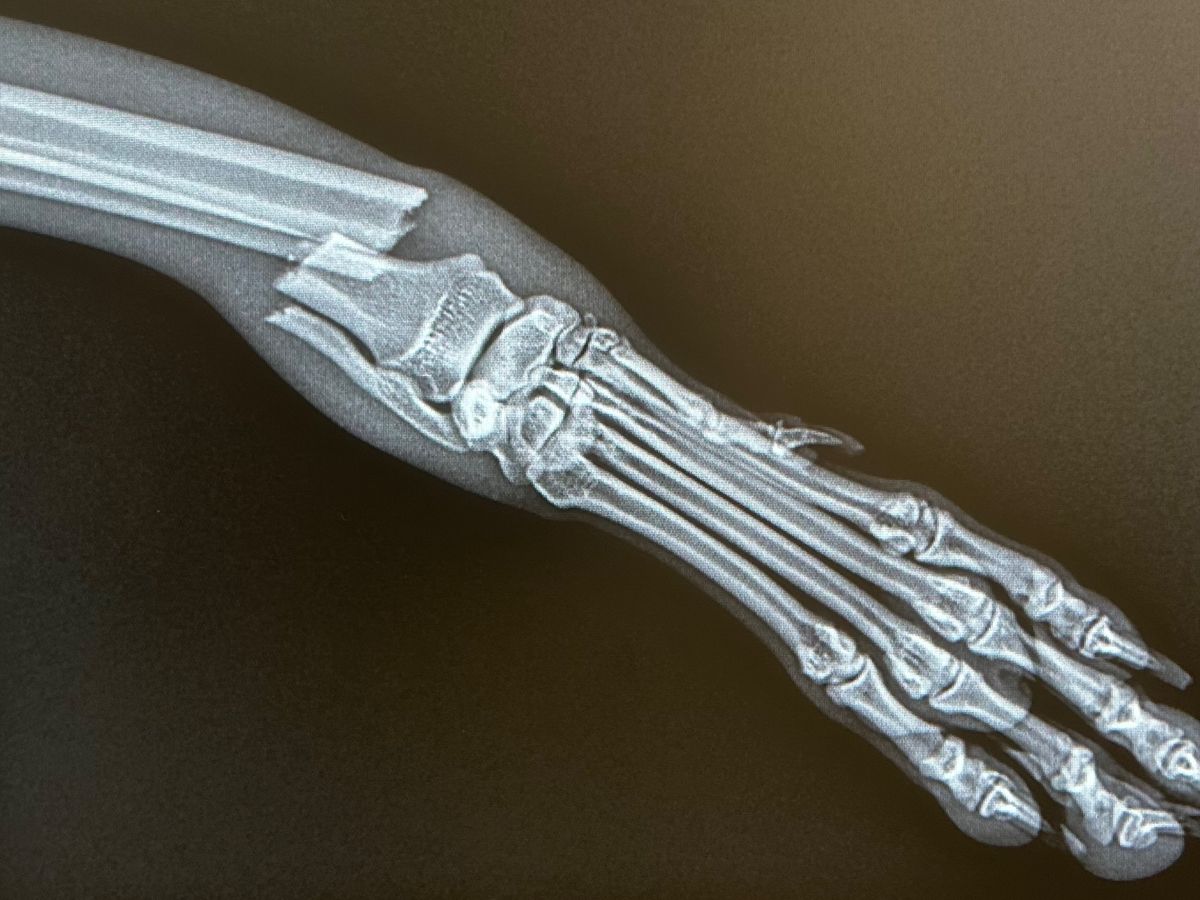

Hi, I’m Sabrina a Vet technician. We rescued a little Greyhound of 1 year old at my job. He jumped from a high place at his house, his paw is broken but the owners couldn’t pay 5000$.

he is young and as potential so we want to give him a chance. We could save his entire paw with the surgery, or we will amputate his entire leg for his confort since it is less expensive. If we wait too long, the paw cannot be fixed…